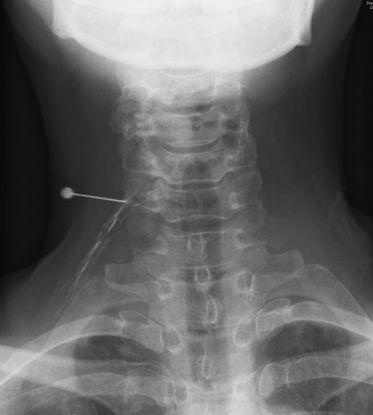

首下がり症候群に対するSHAiR リハビリテーション

(シェアプログラム)

首下がり症候群に対する治療は国内外での様々な研究でリハビリテーションでは効果がないとされ、手術治療が推奨されていました。

650名以上の首下がり症候群の治療経験をもとに独自に開発した有効性の高い治療効果のあるリハビリテーション(シェアプログラム)を実施します。開発当初は2週間の入院が必要な治療でしたが、「自分が受けたい治療を患者様に提供する」「患者様に負担の少ない治療を提供する」という石井総院長の想いから、当クリニックでは、通院治療として導入致しております。

シェアプログラムの内容には、首の筋力や柔軟性を高めるトレーニング、全身の姿勢改善を目的とした姿勢エクササイズなどが含まれており、専門トレーナーがマンツーマンでサポートいたします。短期治療成績は、全患者様の92%に首下がりの改善症状をみとめています(発表済み)(図参照) 。

シェアプログラムは当クリニック独自の治療で、現在国内外の医療機関で、当院のみで実施をしている治療となります。また、首下がりを引き起こす要因の1つである頚部屈筋群のボトックス注射も実施しています。首下がり症候群でお悩みの方、手術を他院で勧められている方は是非一度ご相談ください。

右レントゲン: Urata R, Ishii K, et. al., Medicina 2022より転載